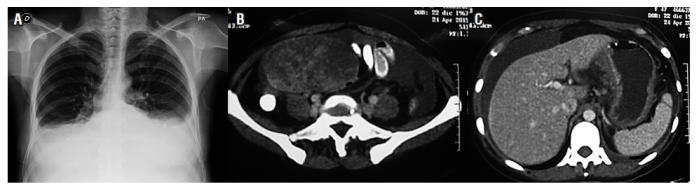

Una tomografía axial computarizada (TAC) de abdomen con contraste (24 de abril del 2015) demostró un leve aumento en el número de ganglios retroperitoneales. El útero estaba aumentado de tamaño con presencia de miomas y masa anexial derecha heterogénea de 110 x 79 x 71 mm de contornos lisos, bien definida y sólida; se encontraba una moderada cantidad de líquido libre en la cavidad; la pared gástrica corporal estaba engrosada; y el peritoneo era nodular (Figura 1).

Figura 1 A. Radiografía de tórax, derrame plural. B. Tomografía con masa anexial derecha. C. Tomografía con líquido peritoneal y engrosamiento de paredes del estómago.